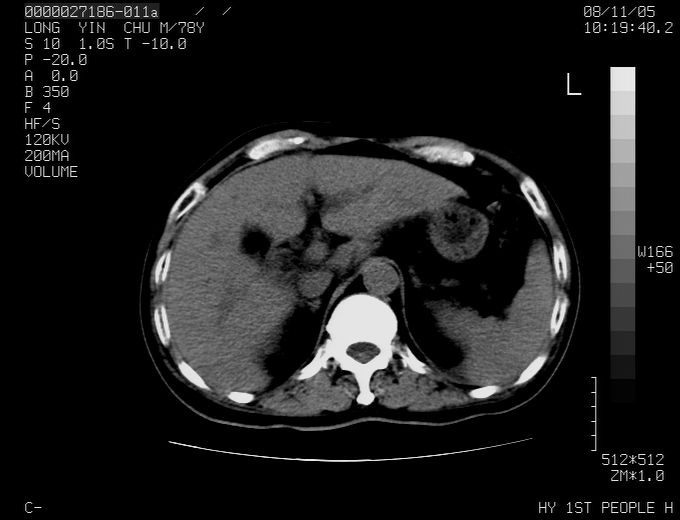

标题: CT16532:M78Y,肝脏病变,请会诊 [打印本页]

标题: CT16532:M78Y,肝脏病变,请会诊

腹胀,腹痛就诊,男性,78岁,外院b超未见异常。

肝ca,脾肾转移

支持脾肾转移瘤,双侧胸腔积液。

考虑弥漫性肝癌并脾及双肾转移.双侧胸水.

图片质量欠佳:多考虑:左侧肾癌。脾脏转移!胸膜转移!

肝脾肾转移瘤可能性大,左肾不除外梗塞,双侧胸水

考虑肝癌并双肾及脾脏转移;双侧胸腔积液。